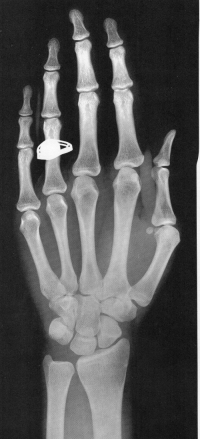

Sexo Feminino

3 meses